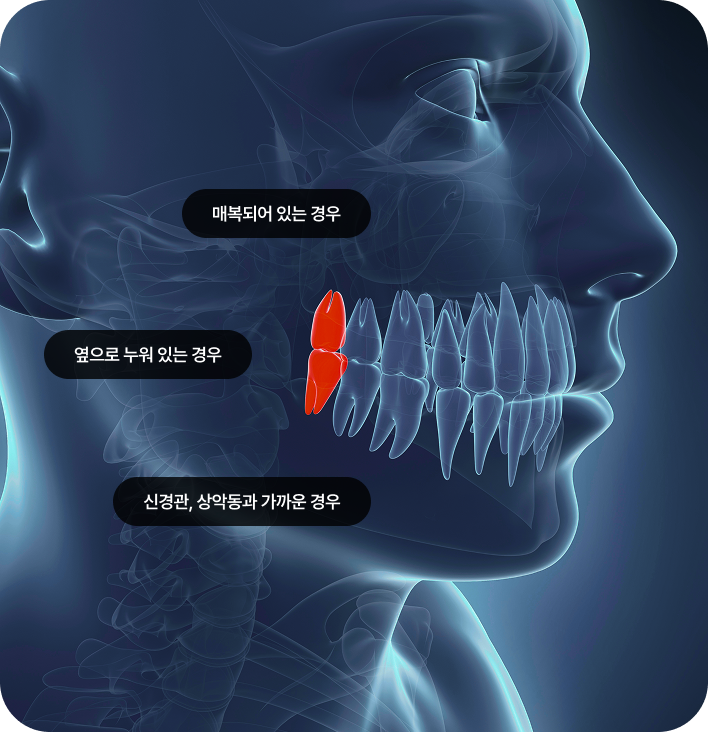

매복 사랑니 발치

임플란트와 사랑니 발치는 외과적 시술로 잇몸을 절개하는 외과적 시술은

짧으면 짧을 수록 시술 후 붓기와 통증이 최소화됩니다.

치과의사 경력 14년차 구강외과 전문의가 빠르고 안전하게, 아프지 않게 수술해 드립니다.